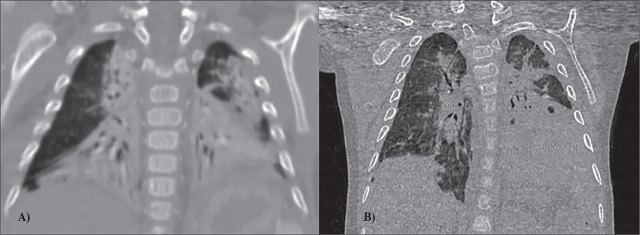

端粒酶逆转录酶(TERT)基因中的致病变体已在成人特发性肺纤维化患者中被发现,但它们与儿童弥漫性肺病的关系尚未被描述。在本研究中,我们介绍了一例五个月大的婴儿,该婴儿之前身体健康,但早期出现呼吸衰竭。根据临床和影像学表现,临床怀疑该病例为巨细胞病毒(CMV)肺炎引发的弥漫性肺部疾病。多器官受累尚未得到证实。考虑到巨细胞病毒性肺炎与早发呼吸衰竭之间可能存在联系,该患者接受了临床外显子组测序,并在 TERT 基因(c.280A>T, p.Lys94Ter)中检测到一个可能致病的新型变异。在分离分析得出阴性结果后,确认了该变异体的新生状态。呼吸支持、抗病毒和抗炎治疗带来了些许益处,然而,在最初发病 18 个月后,出现了不利的结果。总之,重症病毒性肺炎有可能诱发极其罕见的早发性弥漫性肺部疾病,并伴有慢性呼吸功能不全。这与 TERT 基因的致病变异有关。我们对该患者的全面介绍有助于深入了解早发呼吸衰竭病例中遗传因素、临床表现和治疗结果之间错综复杂的相互作用。

The pathogenic variants in the telomerase reverse transcriptase (TERT) gene have been identified in adults with idiopathic pulmonary fibrosis, while their connection to childhood diffuse lung disease has not yet been described. Within this study, we present a case of a five-month-old, previously healthy infant, with early-onset respiratory failure. The clinical suspicion of diffuse lung disease triggered by cytomegalovirus (CMV) pneumonitis was based on clinical and radiological presentation. Multiorgan involvement was not confirmed. Considering the possible connection between CMV pneumonitis and early-onset respiratory failure, clinical exome sequencing was performed and a novel variant, classified as likely pathogenic in the TERT gene (c.280A>T, p.Lys94Ter) was detected. After segregation analysis yielded negative results, the de novo status of the variant was confirmed. Respiratory support, antiviral and anti-inflammatory therapy offered modest benefits, nevertheless, eighteen months after the initial presentation of disease, an unfavourable outcome occurred. In conclusion, severe viral pneumonia has the potential to induce extremely rare early-onset diffuse lung disease accompanied by chronic respiratory insufficiency. This is linked to pathogenic variants in the TERT gene. Our comprehensive presentation of the patient contributes to valuable insights into the intricate interplay of genetic factors, clinical presentations, and therapeutic outcomes in cases of early-onset respiratory failure.